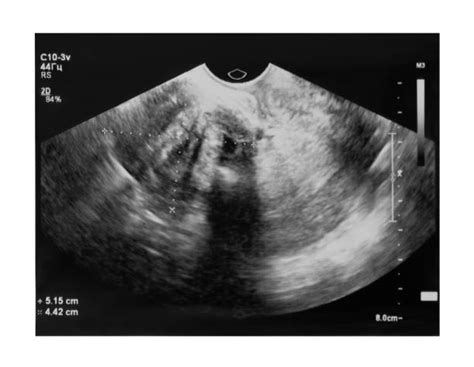

- Ultrasonografia (USG): Základná a najčastejšie používaná zobrazovacia metóda. Najmä transvaginálna USG poskytuje detailný obraz maternice a jej útvarov. USG zobrazí myóm ako guľatý, ostro ohraničený hypoechogénny útvar. V myóme môžu byť viditeľné cystické (anechogénne) alebo degeneratívne zmenené (mixechogénne) časti. USG zvyčajne spoľahlivo určí počet, veľkosť a lokalizáciu myómov.